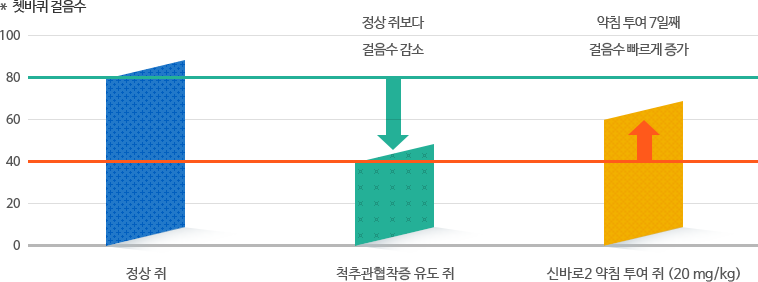

보행운동 능력 회복

척추관협착증을 유도한 쥐는 쳇바퀴 운동 걸음수가 정상쥐보다 절반가량 적었습니다.

신바로2를 투여한 그룹은 7일째부터 걸음수가 눈에 띄게 빨라지면서 보행운동 능력이 회복됐습니다.